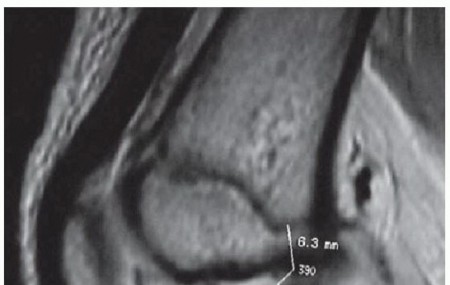

Chapter 40 Arthroscopic Treatment of Elbow Loss of Motion Laith M. Al-Shihabi Chris Mellano Robert W. Wysocki…